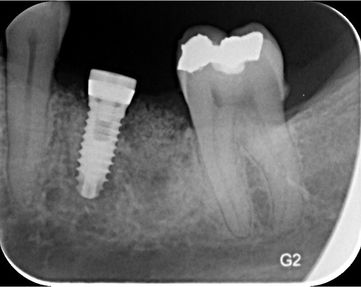

L'implant dentaire est un dispositif, majoritairement en titane, qui remplace la racine d'une ou plusieurs dents manquantes dans le but de supporter une dent ou une prothèse.